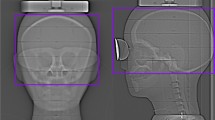

This study was performed using a biplane X-ray device (Azurion7 B20/15; Philips Healthcare, Best, The Netherlands) equipped with flat-panel detectors. An anthropomorphic adult head phantom (PH-3; Kyoto Kagaku Co., Ltd., Kyoto, Japan) was scanned using a whole-brain CBCT protocol (Table 1). All parameters for the CBCT scan were constant and were not changed by a radiological technologist. The CBCT scan was performed by rotating the arc from the left anterior oblique 120° to the right anterior oblique 120° around the posterior aspect of the head phantom (Fig. 1).

CBCT scans were performed using “bismuth shield: eye mask” at varying distances between the surface of the head phantom and bismuth shield, by placing foam pads–from 0 to 20 mm, at every 5 mm (Fig. 3). One and two layers (denoted as “1-ply” and “2-ply”) of “bismuth shield: eye mask” and “bismuth shield: separate” were placed over the eyes of the head phantom (Fig. 4). To evaluate the position dependence of the bismuth shield, the position just above the eyeball of the head phantom was defined as “middle.” “Bismuth shield: separate” was placed 17 mm toward the eye, defined as “inside,” and 17 mm away from the eye, defined as “outside.” The positions corresponding to the lenses were barely covered by protective materials (Fig. 5). Each CBCT scan was performed three times.

2.4 Lens dose measurement with bismuth shield